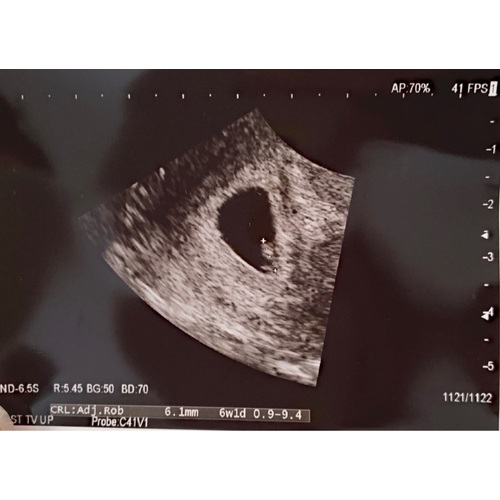

Wij hebben bij zes weken en 2 dagen ook echo gehad en konden het hartje zien kloppen.

Inwendig nog bij 6weken